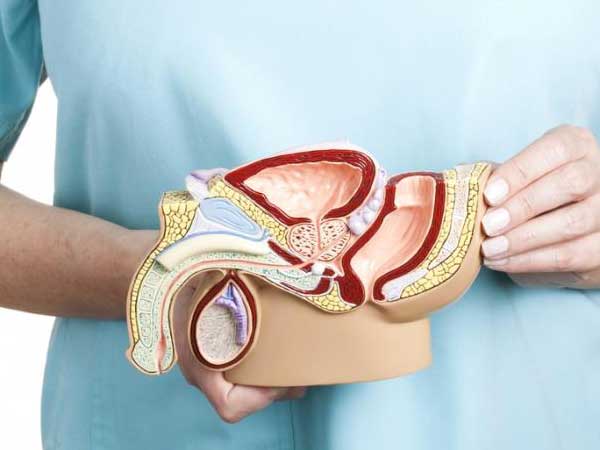

Treatments For Failed Ivf Male Infertility Treatments

Male Infertility Treatments